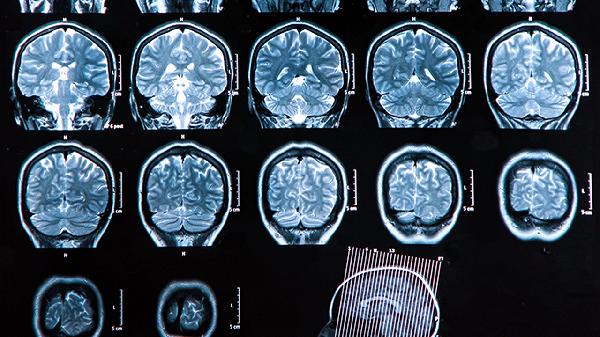

创伤性颅骨缺损早期修补对大脑恢复的帮助

创伤性颅骨缺损早期修补有助于大脑功能恢复,减少并发症,并改善生活质量。早期手术干预可以减少脑组织进一步损伤,促进神经功能康复。